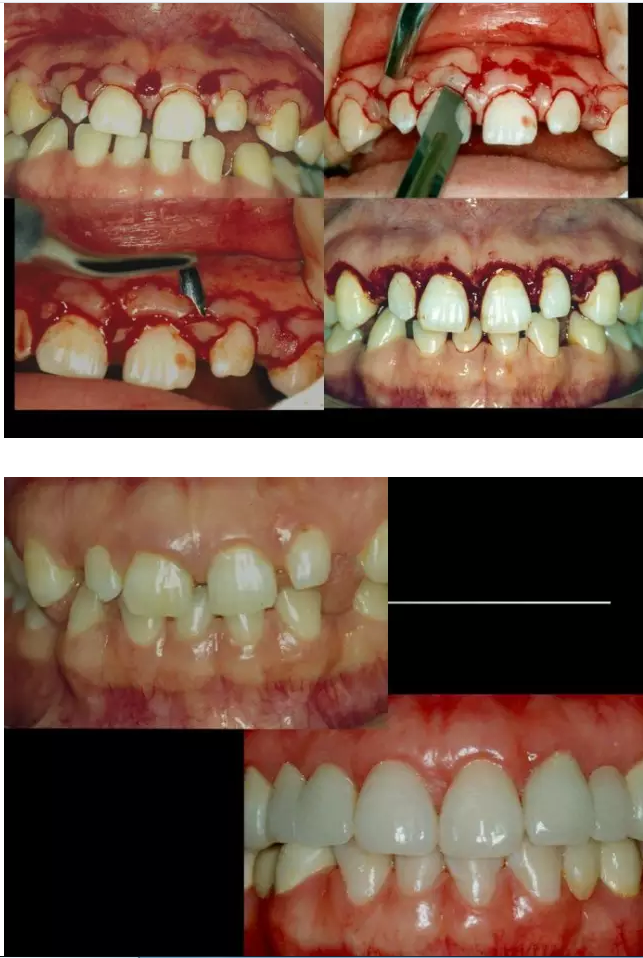

相關(guān)牙周防治